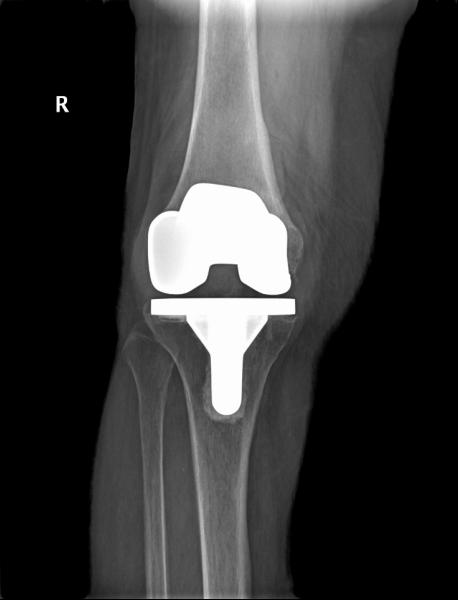

8年前刘奶奶在外院行双膝人工关节表面置换术,术后恢复良好,近2年来反复出现右膝关节疼痛,多次在柳州各大医院门诊及住院诊治,在药物治疗的干预下膝关节疼痛、肿胀时好时坏,来我院门诊诊断右膝关节置换术后感染、假体松动,入住我院关节外科/运动医学科。

图1 X线